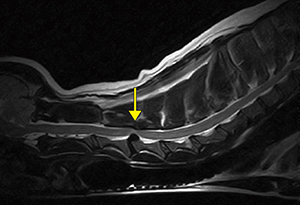

■症例1:イヌ,頸椎ヘルニア

膝コイル,T2WI,SAG,FOV:250mm,

TR/TE:2500/120,スライス厚:3mm,

マトリックス:288×224,scan time:5:48